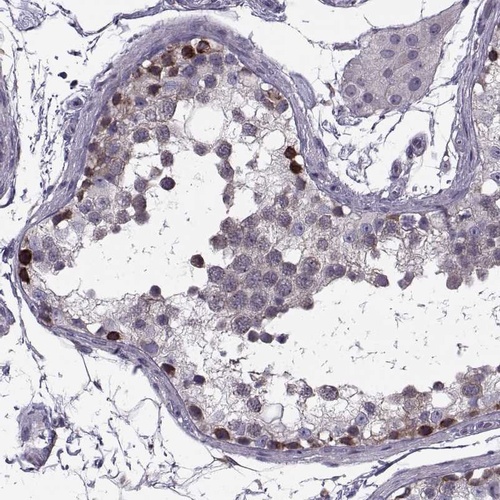

Immunohistochemical staining of human testis shows strong cytoplasmic positivity in cells in seminiferous ducts.